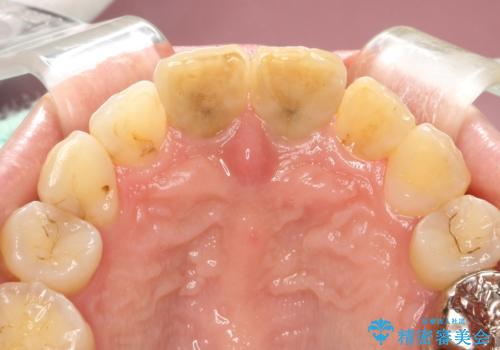

変色した前歯をセラミックできれいに レイヤリングセラミック

前歯のセラミック治療では、他の歯と色調をそろえるのが非常に難しいです。

他の歯に亀裂や白濁など複雑な色合いがある場合、それらをセラミックで再現することも可能ですが、スタンダードのオールセラミックではある程度の同調となります。

かぶせ物の種類: PFZ standard